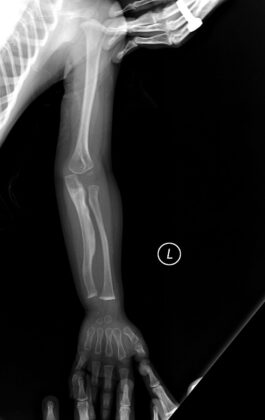

Drengurinn var að verða tveggja ára gamall, þegar að sunnlenskir læknasérfræðingar komumst loksins að þeirri niðurstöðu að hann væri fæddur með alvarlegan beinþynningar sjúkdóm sem heitir: Osteogenesis imperfecta (OI) og honum geta fylgt ýmsir aukakvillar.

Bogin bein og gömul gróin beinbrot.

Móðirin var tíður gestur á Sjúkrahúsi Siglufjarðar og læknum tókst ekki að finna á þessu nokkra læknisfræðilegar útskýringar. Þegar hann byrjaði að skríða, brotnuðu á honum fingur og tær og seinna þegar okkar manneskjulega þörf kom yfir hann, við að reyna að standa uppréttur og ganga, var eins og að fæturnir bognuðu undir blessuðu barninu og varð hann þar af snemma mjög svo hjólbeinóttur og líktist göngulagið mest gömlum hestabónda. Í þessum barnalegu tilþrifum sínum við það eitt að reyna að ganga, datt hann oft og það kostaði hann bæði handleggs og handliðsbrot, með tilheyrandi gifsumbúðum.

Gurrý beinþynningar sérfræðingur veit mikið vel að í dag eru til bæði skurðaðgerðar lausnir sem rétta upp bogin bein og lyf sem styrkja þessi brothættu bein. Hún sér einnig fyrir sér tíðarandann, sem ræður ríkjum þegar þessi læknisfræðilegu ráð eru gefinn og að hún sem og móðir hennar, í umhyggjusamri velvild og hræðslu við að missa blessað barnið frá sér, sköpuðu þetta of verndaða, ófrjálsa og einangraða líf sem bróðir hennar var tilneyddur að lifa.